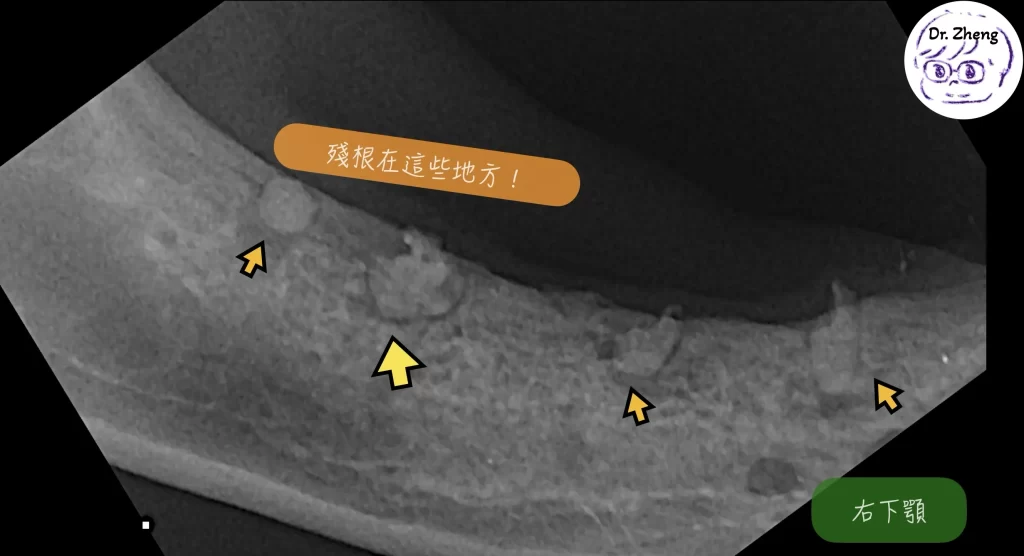

牙科X光檢查發現牙齒殘根

我幫小甜安排了全口牙科X光後發現,原來有4顆齒吸收的牙齒牙冠被拔除,但牙根仍埋在牙齦內未清除!

重點是:要有牙科X光才能正確分類與完整處理。

- 殘根很小,一定要用牙科X光進行診斷和定位